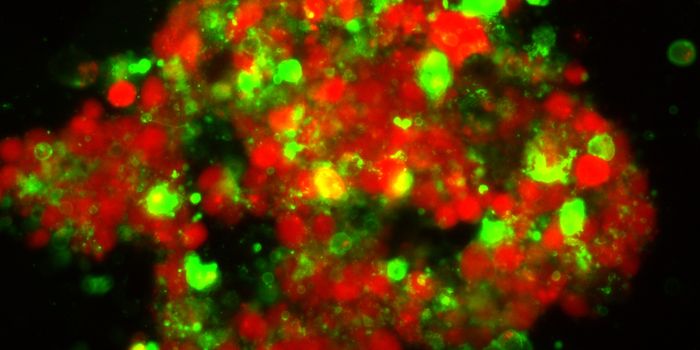

DEC 23, 2015ImmunologyInhibiting large cellular populations of myeloid derived suppressor cells (MDSCs – look up) could be a new therapy ...